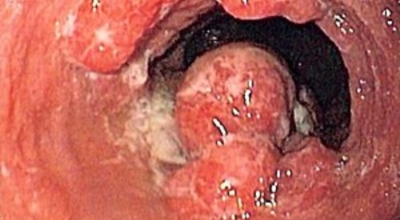

식도암은 다른암에 비교해 사망 가능성이 아주 높은 암이랍니다. 식도암 초기증상 발견 시에는 예후가 매우 좋지만, 2,3기에 발견될 시에는 사망하는 비율이 가파르게 오르게 되어요. 다만 초기에는 증상이 거의 없으므로 문제가 되어요. 초기에 관찰되는 경우는 내시경을 통한 방법말고는 거의 없다고 해요. 그러기에 주기적인 내시경은 필수겠죠.

안타깝지만 식도암 초기증상은 잘 느끼지 못해요. 하지만 방법은 있습니다. 그것은 바로 위 내시경 검사를 받는 것으로 보입니다. 위 내시경 검사를 받을 때 식도를 거쳐서 내시경 검사를 하므로 우리는 꼭 2년에 한번씩, 나이가 50대가 넘었다면 1년에 한번씩 내시경 검사를 받아야 해요.